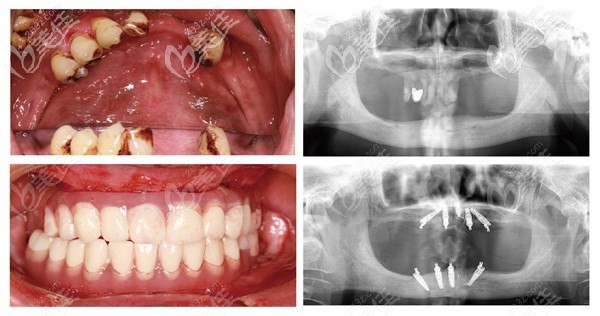

杭州美奧口腔醫(yī)院是經(jīng)相關(guān)部門批準(zhǔn)成立的正規(guī)的私立口腔連鎖機構(gòu),也是一所高端先進的美式口腔機構(gòu),擁有近2000平米的使用面積,開設(shè)了牙齒種植、牙齒矯正、牙齒修復(fù)、牙齒美白、兒童齒科及口腔疾病治療6大特色齒科診療,不斷的引進新的技術(shù),壯大醫(yī)生團隊,自成立至今,美奧口腔在杭州當(dāng)?shù)氐目诒际窍喈?dāng)不錯的。 美奧口腔目前在核心城市,如長沙、常德、、蘇州、烏魯木齊、杭州、天津、合肥、南京、無錫等地開設(shè)詳細(xì)>